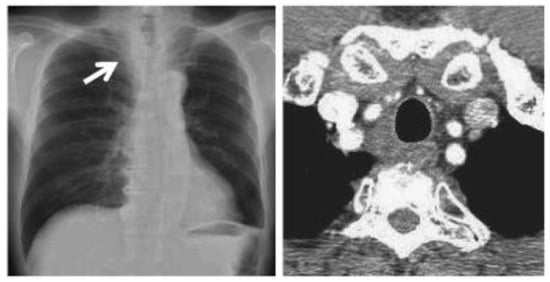

In March 2020, a 35-year-old patient arrived at our department with the results of a recently performed positive biopsy. For this reason, a CT scan of the chest, abdomen, and pelvis with means of contrast was performed in our department. CT examination confirmed the presence of several mediastinal lymph nodes. An anterior mediastinal lymph node with a diameter of (39 × 26 mm), a para-aortic lymph node with a diameter of (35 × 25 mm), a lymph node of the aorta-pulmonary window with a diameter of (30 × 20 mm) as well as several lymph nodes with diameters ranging from (27 × 16 mm) to (23 × 20 mm). Focal pleural thickening of 10 mm was confirmed at the posterior right lower lobe (peri-vertebral) (see Figure 1). For these reasons, it was decided to subject the patient to a cryosurgery intervention procedure as described above.

Figure 1. CT scan image executed.